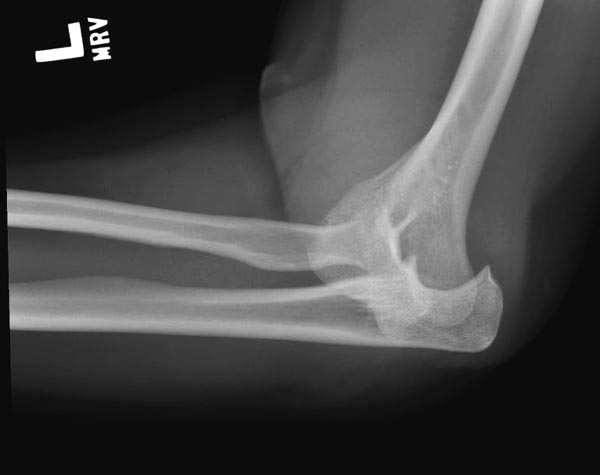

Имя     : 3 Elbow radial head fx.JPG

Тип     : image/jpeg